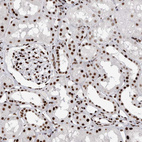

Immunohistochemical staining of human cerebral cortex, gastrointestinal, kidney and lymphoid tissues using Anti-RBM6 antibody HPA027164 (A) shows similar protein distribution across tissues to independent antibody HPA026272 (B).